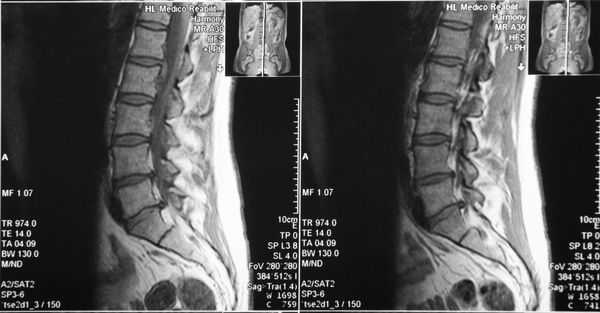

МРТ поясничного отдела позвоночника. 1- выраженная дегидратация межпозвонковых дисков во всех сегментах. 2- дегидратация в сегментах L3-L4, L4-L5 справа (разные пациенты)